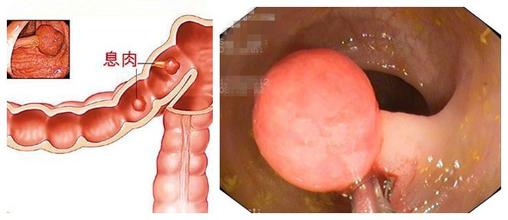

肠息肉

导语 盘锦医生表示:肠息肉是指肠黏膜表面突出的异常生长的组织,在没有确

导语 肠息肉是肠道内的病变,它可小至芝麻、绿豆,也可大至核桃大

导读 肠子上长息肉这一病症在医学上称之为肠息肉。肠息肉是一种良性的病变